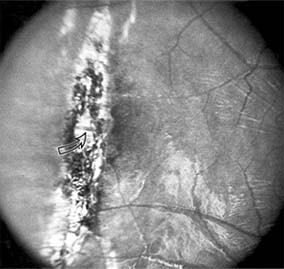

Chapter 10: Retina DISEASES OF THE MACULA AGE-RELATED MACULAR DEGENERATION Age-related macular degeneration is the leading cause of permanent blindness in the elderly. The exact cause is unknown, but the incidence increases with each decade over age 50. Other associations besides age include race (usually Caucasian), sex (slight female predominance), family history, and a history of cigarette smoking. The disease includes a broad spectrum of clinical and pathologic findings that can be classified into two groups: nonexudative ("dry") and exudative ("wet"). Although both types are progressive and usually bilateral, they differ in their manifestations, prognosis, and management. The more severe exudative form accounts for approximately 90% of all cases of legal blindness due to age-related macular degeneration. 1. NONEXUDATIVE MACULAR DEGENERATION Nonexudative age-related macular degeneration is characterized by variable degrees of atrophy and degeneration of the outer retina, retinal pigment epithelium, Bruch's membrane and choriocapillaris. Of the ophthalmoscopically visible changes in the retinal pigment epithelium and Bruch's membrane, drusen are the most typical (Figure 10-1). Drusen are discrete, round, yellow-white deposits of variable size beneath the pigment epithelium and are scattered throughout the macula and posterior pole. With time, they may enlarge, coalesce, calcify, and increase in number. Histopathologically, most drusen consist of focal collections of eosinophilic material lying between the pigment epithelium and Bruch's membrane; they therefore represent focal detachment of the pigment epithelium. In addition to drusen, clumps of pigment irregularly dispersed within depigmented areas of atrophy may progressively appear throughout the macula. The level of associated visual impairment is variable and may be minimal. Fluorescein angiography demonstrates irregular patterns of retinal pigment epithelial hyperplasia and atrophy. Electrophysiologic testing in most patients is normal. There is no generally accepted treatment or means of prevention of this type of macular degeneration. Laser retinal photocoagulation appears to have a beneficial effect on drusen but has not yet been shown to improve visual outcome. Although high plasma levels of antioxidants are associated with a reduced risk of age-related macular degeneration, the use of vitamin supplements does not appear to be preventive. Most patients with macular drusen never experience significant loss of central vision; the atrophic changes may stabilize or progress slowly. However, the exudative stage may develop suddenly at any time, and in addition to regular ophthalmic examinations, patients are given an Amsler grid ( 2. EXUDATIVE MACULAR DEGENERATION Although patients with age-related macular degeneration usually manifest nonexudative changes only, the majority of patients who experience severe vision loss from this disease do so from the development of subretinal neovascularization and related exudative maculopathy. Serous fluid from the underlying choroid can leak through small defects in Bruch's membrane, causing focal detachment of the pigment epithelium. Additional fluid may lead to further separation of the overlying sensory retina, and vision usually decreases if the fovea is involved. Retinal pigment epithelial detachments may spontaneously flatten, with variable visual results, and leave a geographic area of depigmentation at the involved site. Ingrowth of new vessels from the choroid into the subretinal space is the most important change that predisposes patients with drusen to macular detachment and irreversible loss of central vision. These new vessels grow in a flat cartwheel or sea-fan configuration away from their site of entry into the subretinal space. The clinical changes of early subretinal neovascularization are subtle and may be easily overlooked; during this occult stage of new vessel formation, the patient is asymptomatic, and the new vessels may not be apparent either ophthalmoscopically or angiographically. The ophthalmologist must maintain a high index of suspicion that subretinal neovascularization is present whenever a patient with evidence of age-related macular degeneration has sudden or recent central vision loss, including blurred vision, distortion, or a new scotoma. If the fundus examination reveals subretinal blood, exudate, or a grayish-green choroidal lesion in the macula, there is great likelihood that neovascularization is present, and a fluorescein or indocyanine green angiogram should be obtained promptly to determine if a treatable lesion can be identified. Although some subretinal neovascular membranes may spontaneously regress, the natural course of subretinal neovascularization in age-related macular degeneration is toward irreversible loss of central vision over a variable period of time. The sensory retina may be damaged by long-standing edema, detachment, or underlying hemorrhage. Furthermore, a hemorrhagic detachment of the retina may undergo fibrous metaplasia, resulting in an elevated subretinal mass called a disciform scar. This elevated fibrovascular mound of variable size represents the cicatricial end stage of exudative age-related macular degeneration. It is usually centrally located and results in permanent loss of central vision. Treatment In the absence of subretinal neovascularization, no medical or surgical treatment of serous retinal pigment epithelial detachment is of proved benefit. The use of parenteral alpha interferon, for example, has not been effective for this disease. However, if a well-defined extrafoveal ( Krypton laser photocoagulation of juxtafoveal (<200 Following successful photocoagulation of a subretinal neovascular membrane, recurrent neovascularization either contiguous with or remote from the laser scar may occur in one-half of cases by 2 years. Recurrence is often accompanied by severe vision loss, so that careful monitoring with Amsler grids, ophthalmoscopy, and angiography is essential. Low-dose radiotherapy has provided encouraging results in patients with subfoveal neovascularization. Patients with impaired central vision in both eyes may benefit from a variety of low vision aids. CENTRAL SEROUS CHORIORETINOPATHY Central serous chorioretinopathy is characterized by serous detachment of the sensory retina as a consequence of focal leakage of fluid from the choriocapillaris through a defect in the retinal pigment epithelium (Figures 10-2 and 10-3). This disease typically affects young to middle-aged men and may be related to life stress events. Most patients present with the sudden onset of blurred vision, micropsia, metamorphopsia, and central scotoma. Visual acuity is often only moderately decreased and may be improved to near-normal with a small hyperopic correction. The diagnosis is made by slitlamp examination of the fundus; the presence of serous detachment of the sensory retina in the absence of ocular inflammation, subretinal neovascularization, an optic pit, or a choroidal tumor is diagnostic. The retinal pigment epithelial lesion appears as a small, round or oval, yellowish-gray spot that is variable in size and may be difficult to detect without the aid of fluorescein angiography. Fluorescein dye leaking from the choriocapillaris may accumulate below the pigment epithelium or sensory retina, resulting in a variety of patterns including the well-recognized smokestack configuration. Approximately 80% of eyes with central serous chorioretinopathy undergo spontaneous resorption of subretinal fluid and recovery of normal visual acuity within 6 months after the onset of symptoms. Despite normal acuity, however, many patients have a mild permanent visual defect, such as a decrease in color sensitivity, micropsia, or relative scotoma. Twenty to 30 percent of patients will have one or more recurrences of the disease, and complications-including subretinal neovascularization and chronic cystoid macular edema-have been described in patients with frequent and prolonged serous detachments. The cause of central serous chorioretinopathy is unknown; there is no convincing evidence that the disease is either infectious or due to retinal pigment epithelial dystrophy. Argon laser photocoagulation directed to the active leak significantly shortens the duration of the sensory detachment and hastens the recovery of central vision, but there is no evidence that prompt photocoagulation reduces the chance of permanent loss of visual function. Although the complications of retinal laser photocoagulation are few, it is probably not advisable to recommend immediate photocoagulation treatment in all patients with central serous chorioretinopathy. The duration and location of disease, the condition of the fellow eye, and occupational visual requirements are all considerations upon which treatment decisions are based. MACULAR EDEMA Retinal edema involving the macula may be associated with a variety of intraocular inflammatory diseases, retinal vascular diseases, intraocular surgery, inherited or acquired retinal degenerations, medications, macular membranes, or unknown causes. Macular edema may be diffuse, with nonlocalized intraretinal fluid causing thickening of the macula. When edema fluid accumulates in honeycomb-like spaces of the outer plexiform and inner nuclear layers, it is called cystoid macular edema. On fluorescein angiography, fluorescein dye leaks from the perifoveal retinal capillaries and accumulates in a flower-petal pattern about the fovea (Figure 10-4). The most widely recognized association with cystoid macular edema is intraocular surgery. Approximately 50% of eyes undergoing uneventful intracapsular cataract extraction and 20% of eyes undergoing extracapsular cataract extraction develop angiographic cystoid macular edema. Clinically significant edema usually occurs within 4-12 weeks postoperatively, but in some instances its onset may be delayed for months or years. Many patients with cystoid macular edema of less than 6 months' duration have self-limited leakage that will resolve without treatment. Topical or local (or both) anti-inflammatory therapy may be of value in restoring visual acuity in some patients with chronic postoperative macular edema. YAG laser vitreolysis (see Chapter 24) and surgical vitrectomy may be of benefit when the macular edema is associated with vitreous tissue incarcerated in the cataract wound or adherent to anterior segment structures. When an intraocular lens implant is the cause of postoperative macular edema due to its design, positioning, or inadequate fixation, removal of the lens implant can be considered. INFLAMMATORY DISORDERS INVOLVING THE MACULA Presumed Ocular Histoplasmosis Syndrome (Figures 10-5, 10-6 and 10-7) In this disease, serous and hemorrhagic detachments of the macula are associated with multiple peripheral atrophic chorioretinal scars and peripapillary chorioretinal scarring (see Chapter 7). The syndrome usually occurs in healthy patients between the third and sixth decades of life, and the scars are probably caused by an antecedent subclinical systemic infection with Histoplasma capsulatum. The macular detachments are due to subretinal neovascularization, and the visual prognosis depends on the proximity of the neovascular membrane to the center of the fovea. If the membrane extends inside the foveal avascular zone, only 15% of eyes will retain 20/40 vision. A macular scar may change over time, and 10% of patients with normal maculae will develop new atrophic scars in this region. The relative risk of developing macular subretinal neovascularization in the second eye of an affected patient is significant, and these patients should be instructed in the frequent use of the Amsler grid and the importance of prompt examination when changes are detected. Argon laser photocoagulation of a subretinal neovascular membrane outside the foveal avascular zone in symptomatic patients is of value in preventing severe vision loss. The surgical removal of submacular membranes may prove useful in preserving vision. Acute Multifocal Posterior Placoid Pigment Epitheliopathy (AMPPPE) AMPPPE typically affects healthy young patients who develop rapidly progressive bilateral vision loss in association with ophthalmoscopically visible multifocal flat gray-white subretinal lesions involving the pigment epithelium (Figure 10-8). The cause of this disease, which in many instances is associated with evidence of an influenza-like illness, is unknown; the course and nature of the illness suggests the possibility of viral infection. The characteristic feature of the disease is the rapid resolution of the fundus lesions and a delayed return of visual acuity to near-normal levels. Although the prognosis for visual recovery in this acute self-limited disease is good, many patients will identify small residual paracentral scotomas when carefully tested. Extensive pigmentary changes remaining during the late stages of AMPPPE may mimic widespread retinal degeneration; the clinical history and normal electrophysiologic findings aid in this differential diagnosis. Geographic Helicoid Peripapillary Choroidopathy This is a chronic progressive and recurrent multifocal inflammatory disease of the retinal pigment epithelium, choriocapillaris, and choroid. It characteristically involves the juxtapapillary retina and extends radially to involve the macula and peripheral retina. The active stage manifests itself as sharply demarcated gray-yellow lesions with irregular borders that appear to involve the pigment epithelium and choriocapillaris. Vitritis, anterior uveitis, and subretinal neovascularization have been associated with this disorder. Involvement is usually bilateral, and the cause is unknown. The natural history of this indolent inflammatory disease is variable and may correlate with the presence of disease in the fellow eye. Local or systemic corticosteroid treatment may be of benefit when active inflammation is present; laser photocoagulation is administered as indicated for the complication of subretinal neovascularization. Vitiliginous Chorioretinitis (Birdshot Retinochoroidopathy) This is a syndrome characterized by diffuse cream-colored patches at the level of the pigment epithelium and choroid, retinal vasculitis associated with cystoid macular edema, and vitritis. The associations with HLA-A29 and with retinal S-antigen suggest that this disease has a genetic predisposition and that retinal autoimmunity plays a role in its manifestations. In many cases, electroretinography, electro-oculography, and dark adaptation studies are abnormal. The course of the disease is that of exacerbation and remission with variable visual outcomes; visual loss has been attributed to chronic cystoid macular edema, optic atrophy, macular scarring, or subretinal neovascularization. Corticosteroid therapy has not proved effective against this disease. Acute Macular Neuroretinopathy Acute macular neuroretinopathy is characterized by the acute onset of paracentral scotomas and mild visual acuity loss accompanied by wedge-shaped parafoveal retinal lesions in the deep sensory retina of one or both eyes. The macular lesions are subtle, reddish-brown, and best seen with a red-free light. The patients are usually young adults with a history of acute viral illness. While the retinal lesions may fade, the scotomas tend to persist and remain symptomatic. Multiple Evanescent White Dot Syndrome This is an acute and self-limited unilateral disease that affects mainly young women and is characterized clinically by multiple white dots at the level of the pigment epithelium, vitreal cells, and transient electroretinographic abnormalities. The cause is unknown. There is no evidence of associated systemic disease. The retinal lesions gradually regress in a matter of weeks, leaving only minor retinal pigment epithelial defects. ANGIOID STREAKS Angioid streaks appear as irregular, jagged tapering lines that radiate from the peripapillary retina into the macula and peripheral fundus (Figure 10-9). The streaks represent linear crack-like dehiscences in Bruch's membrane. The lesions are rarely noted in children and probably develop in the second or third decade of life. Early in the disease the streaks are sharply outlined and red-orange or brown. Subsequent fibrovascular tissue growth may partially or totally obscure the streak margins. Nearly 50% of patients with angioid streaks have an associated systemic disease. Pseudoxanthoma elasticum, Paget's disease of bone, Ehlers-Danlos syndrome, and several hemoglobinopathies and hemolytic disorders have been associated with this retinal disease, but the most common association is with age-related degeneration of Bruch's membrane. Patients with angioid streaks should be warned of the potential risk of choroidal rupture from even relatively mild eye trauma. Older patients with the disease are at risk of developing serous and hemorrhagic detachments of the retina as a consequence of subretinal neovascularization. Laser treatment may be used to photocoagulate extrafoveal neovascular membranes; however, other neovascular membranes are likely to occur. Prophylactic treatment of angioid streaks before subretinal neovascularization develops is not recommended. MYOPIC MACULAR DEGENERATION Pathologic myopia is one of the leading causes of blindness in the United States and is characterized by progressive elongation of the eye with subsequent thinning and atrophy of the choroid and pigment epithelium in the macula. Peripapillary chorioretinal atrophy and linear breaks in Bruch's membrane ("lacquer cracks") are characteristic findings on ophthalmoscopy (Figure 10-10). The degenerative changes of the macular pigment epithelium resemble those found in the older patient with age-related macular degeneration. A characteristic lesion of this disease is a raised, circular, pigmented macular lesion called a Fuchs spot. Most patients are in the fifth decade when the degenerative macular changes cause a slowly progressive loss of vision; rapid loss of visual acuity is usually caused by serous and hemorrhagic macular degeneration overlying a subretinal neovascular membrane. Fluorescein angiography in patients with pathologic myopia may show delayed filling of choroidal and retinal blood vessels. Angiography is helpful in identifying and locating the site of subretinal neovascularization in patients who develop serous or hemorrhagic detachments of the macula. Because of the frequent close proximity of the subretinal neovascular membrane to the foveola in these patients, laser photocoagulation may not be possible. As subretinal neovascular membranes tend to remain small and because photocoagulation-associated chorioretinal atrophy tends to progress in patients with pathologic myopia, retinal laser treatment is not as beneficial as in other diseases associated with macular subretinal neovascularization. The chorioretinal changes of pathologic myopia predispose the retina to breaks and thus to retinal detachment. Peripheral retinal findings may include paving stone degeneration, pigmentary degeneration, and lattice degeneration. Retinal breaks usually occur in areas involved with chorioretinal lesions, but they also arise in areas of apparently normal retina. Some of these breaks, particularly those of the "horseshoe" and round retinal tear type, will progress to rhegmatogenous retinal detachment. MACULAR HOLE A macular hole is a partial or full-thickness absence of the sensory retina in the macula. This disorder occurs most often in elderly women and is associated with elevated plasma fibrinogen levels. The typical finding on biomicroscopy of the symptomatic eye is a full-thickness, round or oval, sharply defined hole measuring one-third disk diameter in the center of the macula, which may be surrounded by a ring detachment of the sensory retina (Figure 10-11). With a full-thickness macular hole, visual acuity is impaired and metamorphopsia, as well as a central scotoma, are present on the Amsler grid. An operculum of retinal tissue may overlie the macular hole. Tangential traction from epiretinal vitreous cortex plays an important role in the pathogenesis of macular hole. Early stages of macular hole formation, such as a deep foveal yellow spot or ring, may be reversible as the posterior vitreous cortex spontaneously separates from the retina. Therapy for macular hole disease involves reattaching and potentially restoring function to the retina overlying the cuff of subretinal fluid surrounding the hole. While the anatomic results of vitrectomy surgery to close macular holes are encouraging, the clinical benefits are still under study. EPIRETINAL MACULAR MEMBRANES Fibrocellular membranes may proliferate on the surface of the retina, either in the macula or peripheral retina. Contraction or shrinkage of these epiretinal membranes may cause varying degrees of visual distortion, intraretinal edema, and degeneration of the underlying retina. Biomicroscopy usually shows retinal wrinkles and vessel tortuosity and may rarely also show retinal hemorrhages, cotton-wool spots, serous retinal detachment, and macular hole; a posterior vitreous detachment is nearly always present (Figure 10-12). Disorders associated with epiretinal membranes include retinal tears with or without rhegmatogenous retinal detachment, vitreous inflammatory diseases, trauma, and a variety of retinal vascular diseases. Patients with macular distortion and vision loss caused by epiretinal membrane contraction are usually left with stable visual acuity, suggesting that membrane contraction is a short-lived and self-limited process. Surgical peeling of severe epiretinal membranes can be performed successfully, but regrowth of epiretinal tissues occurs in some cases. There is no role for photocoagulation in the treatment of epiretinal macular membrane disease. TRAUMATIC MACULOPATHY Blunt trauma to the anterior segment of the eye may cause a contrecoup injury to the retina called commotio retinae. The retina develops a gray-white color that affects primarily the outer retina and may be confined to the macular area (Berlin's edema) or may involve extensive areas of the peripheral retina. The retinal whitening in the macular area may clear completely, or impairment of central vision may be permanent and associated with a pigmented retinal scar (Figure 10-13) or a macular hole. Trauma similar to that which causes Berlin's edema may also cause choroidal rupture with subretinal hemorrhage and permanent central vision loss. In addition to blunt trauma, several other traumatic injuries involving the macula are of importance. Purtscher's retinopathy is characterized by multiple patches of superficial retinal whitening and retinal hemorrhages in each eye of a patient after severe compression injury to the head or trunk. Terson's syndrome is seen in approximately 20% of patients after traumatic (or spontaneous) subarachnoid or subdural hemorrhage and is characterized by vitreous and superficial macular hemorrhage. Solar retinopathy refers to a specific foveolar lesion that occurs after sun-gazing and is best described as a usually bilateral sharply circumscribed and often irregularly shaped partial-thickness hole or depression in the center of the fovea. MACULAR DYSTROPHIES Macular dystrophies differ from degenerations in that the former are inherited, though not necessarily evident at birth, and are not associated with systemic diseases. Most often the disorder is restricted to the macula; it may be symmetric or asymmetric, but eventually both eyes are affected. In the early stages of some of these disorders the visual acuity may be reduced while the macular changes are subtle or absent on ophthalmoscopy, and the patient's complaint may be dismissed as spurious. Conversely, in other macular dystrophies, the ophthalmoscopic changes may be very striking at a time when the patient is free of visual symptoms. One method of classifying the more common macular dystrophies is to consider the presumptive anatomic layer or layers of the retina involved (Table 10-1). X-Linked Juvenile Retinoschisis This is a congenital disease of males characterized by a macular lesion called "foveal schisis." On slitlamp examination, foveal schisis appears as small superficial retinal cysts arranged in a stellate pattern accompanied by radial striae centered in the foveal area (Figure 10-14). Visual acuity is usually between 20/40 and 20/200; peripheral visual field abnormalities are present in the 50% of patients with associated peripheral retinoschisis. The posterior pole appears normal on fluorescein angiography, and this may be helpful in the clinical differentiation from cystoid macular edema. B wave abnormalities on the electroretinogram are consistent with the histopathologic finding of intraretinal splitting in the nerve fiber layer. Cone-Rod Dystrophies The cone-rod dystrophies constitute a relatively rare group of disorders that may be regarded as a single entity showing variable expressivity. Most cases are sporadic, but familial cases are usually transmitted by an autosomal dominant inheritance pattern. Cone-rod dystrophy is characterized by predominant involvement of the cone photoreceptors with progressive color vision defects and associated loss of visual acuity. A bilateral and symmetric bulls-eye pattern of depigmentation and a corresponding zone of hyperfluorescence surrounding a central nonfluorescent spot (similar to that seen in chloroquine retinopathy) are the most commonly described biomicroscopic and angiographic changes in these patients (Figure 10-15). As the disease progresses, the electroretinogram shows marked loss of cone function associated with a slight to moderate loss of rod function. Histopathologic study shows absence of macular and paramacular photoreceptors, and there is associated pigment epithelium degeneration. Fundus Albipunctatus Fundus albipunctatus is an autosomal recessive nonprogressive dystrophy characterized by a myriad of discrete small white dots at the level of the pigment epithelium sprinkled about the posterior pole and midperiphery of the retina. Patients are night-blind with normal visual acuity, normal visual fields, and normal color vision. While the electroretinogram and electro-oculogram are usually normal, dark adaptation thresholds are markedly elevated. Retinitis punctata albescens is the less common progressive variant of this dystrophy. Fundus Flavimaculatus (Stargardt's Disease) This is a bilateral and symmetric autosomal recessive disorder characterized by multiple yellow-white fleck lesions of variable size and shape confined to the retinal pigment epithelium (Figure 10-16). Many patients suffer central visual loss in childhood; however, macular involvement and the ultimate visual outcome are variable. Fluorescein angiography is important in differentiating flecks from drusen; the former are usually hypofluorescent. The electroretinogram and electro-oculogram are usually normal. Histopathologic abnormalities are confined to the pigment epithelium; the yellow flecks seen clinically are dense accumulations of lipofuscin within engorged pigment epithelial cells. Vitelliform Dystrophy (Best's Disease) Vitelliform dystrophy is an autosomal dominant disorder with variable penetrance and expressivity with onset usually in childhood. The ophthalmoscopic appearance is variable and ranges from a mild pigmentary disturbance within the fovea to the typical vitelliform or "egg yoke" lesion located within the central macula (Figure 10-17). This characteristic cyst-like lesion is generally quite round and well demarcated and contains homogeneous opaque yellow material lying at the apparent level of the retinal pigment epithelium. The "egg yoke" may degenerate and be associated with subretinal neovascularization, subretinal hemorrhage, and extensive macular scarring. Visual acuity often remains good, and the electroretinogram is normal; the distinctly abnormal electro-oculogram is the hallmark of this disease. PREVIOUS | NEXT Page: 1 | 2 | 3 | 4 | 5 | 6 | 7 | 8 | 9 10.1036/1535-8860.ch10 |